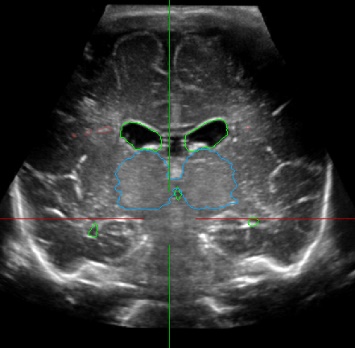

Figure 1: (a) and (b) Manual segmentation of thalami (blue), CVS (green) and PWML (red) in a reconstructed 3D cUS acquisition of a premature infant, (c) 3D cUS manual segmentation and (d) corresponding 3D MRI automatic segmentation of PWMLs (red) in the same premature infant.

Le but de ce stage est d’étudier puis de développer des modèles d’apprentissage automatique pour la détection-segmentation des lésions cérébrales (PWML figure 1) et leur suivi sur plusieurs examens, en utilisant des modèles supervisés pour la segmentation (ex : TransU-Net [2], Swin-UNet [3] ou Mask R-CNN [4]) et entrainés pour chaque temps d’examen (approche statique supervisée). Dans l’idée d’alléger l’annotation du médecin pour chaque structure, on propose d’aborder une approche dynamique semi-supervisée inspirée des méthodes de segmentation de séquences vidéos [5]. Ces méthodes dites VOS (Video Object Segmentation) basées sur les transformeurs ont été développées pour la mise en correspondance des pixels entre l’image (frame) de référence avec l’image cible (Query frame) atteignant de très bonnes performances [5].